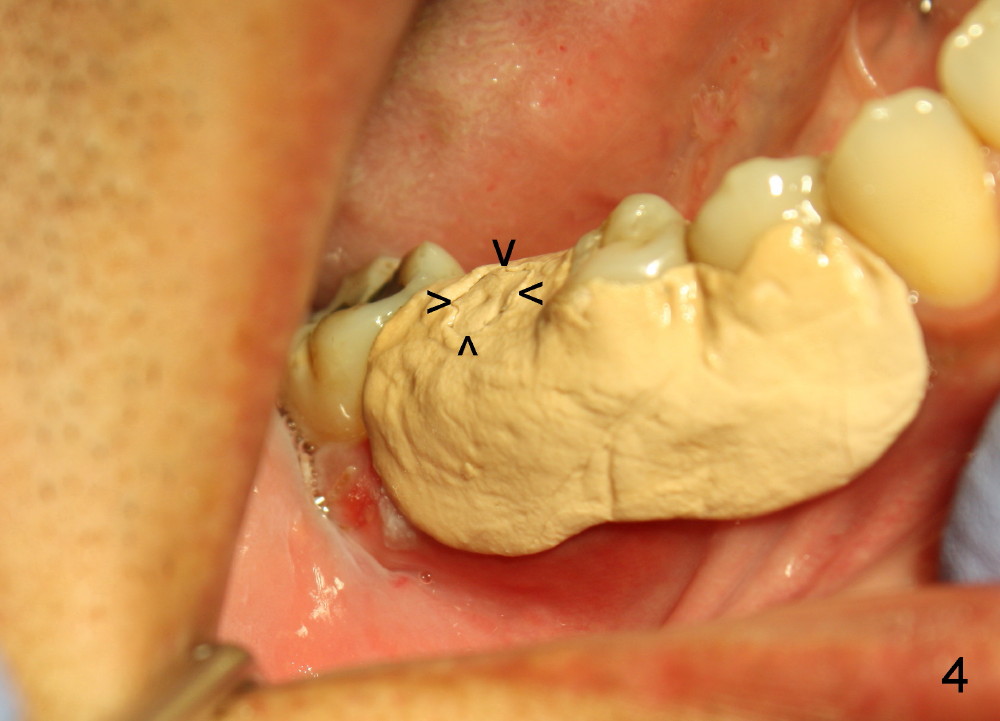

Due to the presence of the abutment (Fig.4 arrowheads), the perio dressing remains in place 7 days postop.

Three weeks postop, the gingiva is healthy around the implant (Fig.5 I). There is no symptom or sign of the infection (>, as compared to Fig.1). The abutment has accomplished its transient function (A, the perio dressing having dislodged) and is subsequently removed (Fig.6, to reduce micromovement of the implant and cheek and tongue bite). The 7 mm implant (I) does not look too big in its new home (alveolus). Four months postop, the mesial socket appears to have normal bony trabecular patterns (Fig.7, as compared to Fig.3).